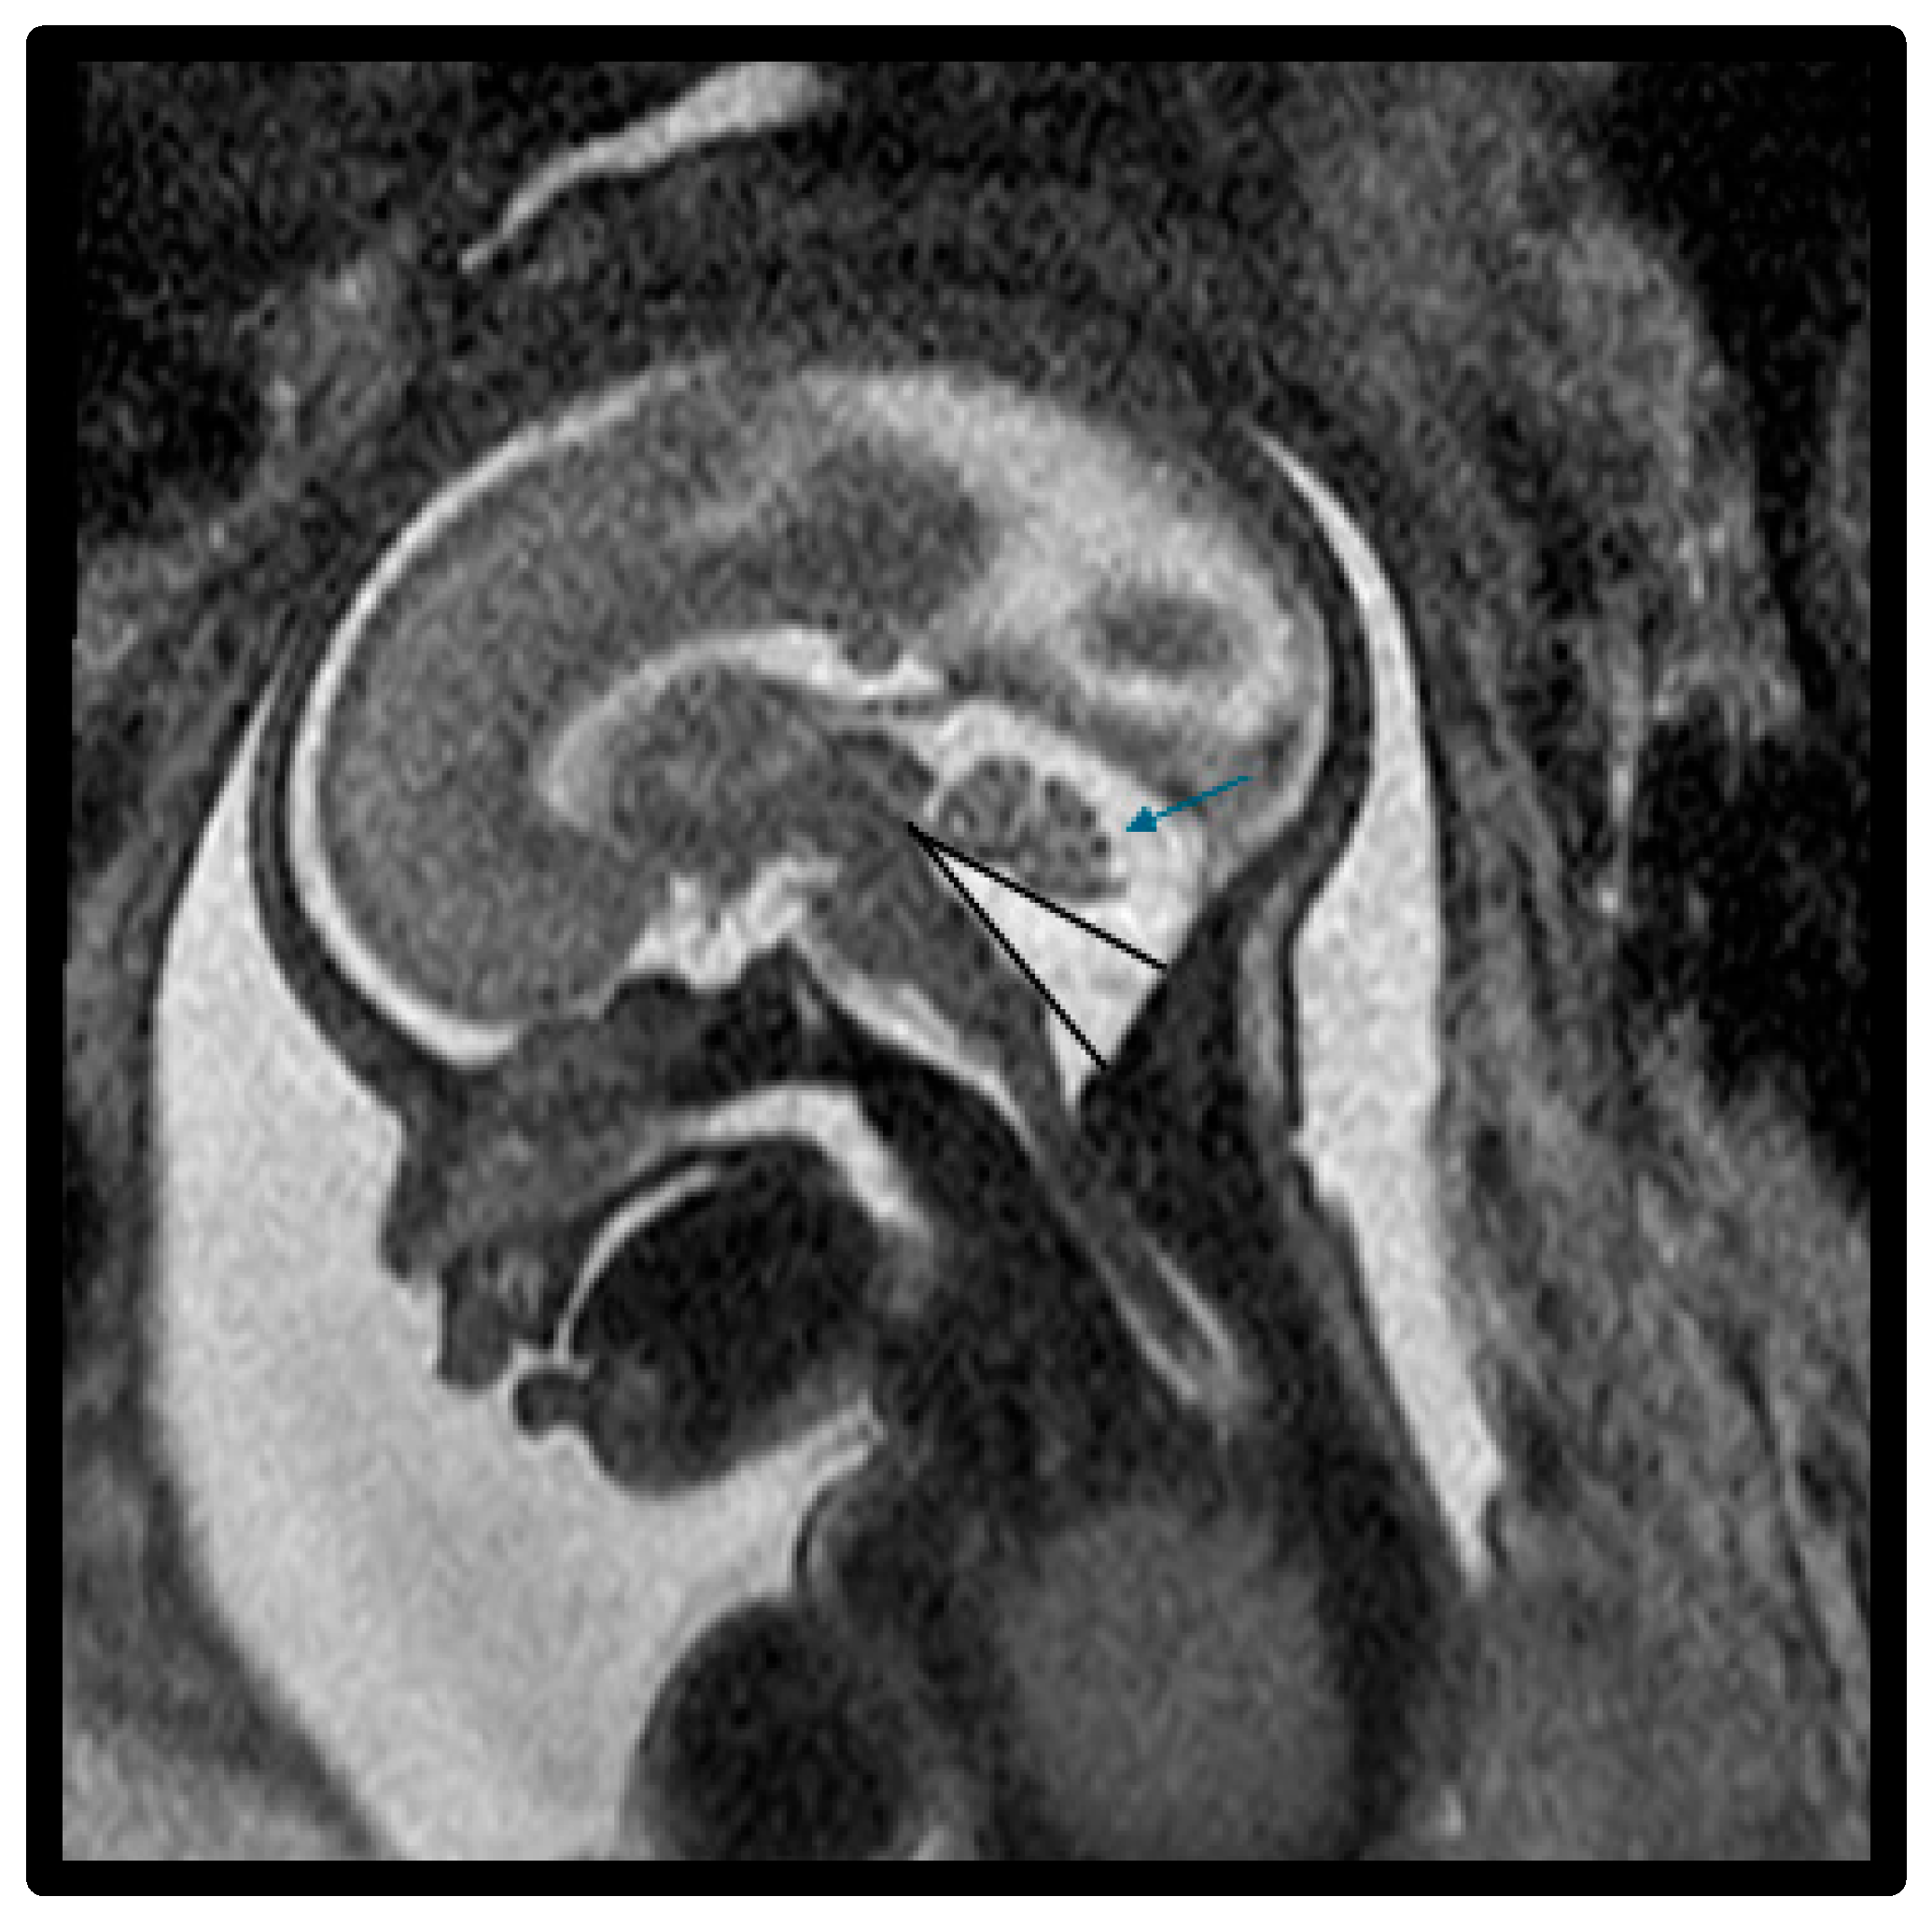

- Bernardo, S.; Vinci, V.; Saldari, M.; Servadei, F.; Silvestri, E.; Giancotti, A.; Aliberti, C.; Porpora, M.G.; Triulzi, F.; Rizzo, G.; et al. Dandy-Walker malformation: Is the ‘tail sign’ the key sign? Prenat. Diagn. 2015, 35, 1358–1364. [Google Scholar] [CrossRef] [PubMed]

- Whitehead, M.T.; Vezina, G.; Schlatterer, S.D.; Mulkey, S.B.; Plessis, A.J. Taenia-tela choroidea complex and choroid plexus location help distinguish Dandy-Walker malformation and Blake pouch cysts. Pediatr. Radiol. 2021, 51, 1457–1470. [Google Scholar] [CrossRef] [PubMed]

- Paladini, D.; Donarini, G.; Parodi, S.; Volpe, G.; Fulcheri, E. Hindbrain morphometry and choroid plexus position in differential diagnosis of posterior fossa cystic malformations. Ultrasound Obstet. Gynecol. 2019, 54, 207–214. [Google Scholar] [CrossRef] [PubMed]